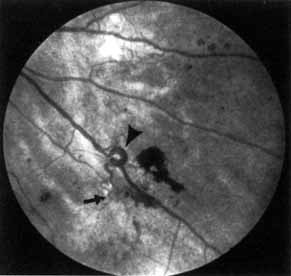

OPTIC NEUROPATHY

As demonstrated by increased latency and decreased amplitude of the visual evoked potential, many patients with diabetes without retinopathy have subclinical optic neuropathy.269,270 In addition, patients with diabetes can develop two types of acute optic neuropathy. The first, anterior ischemic optic neuropathy (AION) is identical to that seen in patients without diabetes. The patients report a sudden decrease in visual acuity or a sudden visual field loss.271–273 The main ocular finding is a “pale swelling” of the optic nerve head with, considering the degree of disc edema, very few hemorrhages (Fig. 27). On fluorescein angiography segmental nonfilling or slow filling is seen (Fig. 27). An afferent pupillary defect (Marcus Gunn) is nearly always present. Visual fields commonly show altitudinal or nerve fiber bundle defects. The disc progresses to optic atrophy (Fig. 27), and improvement in visual function is rare.

Fig. 27 A. Right eye: ischemic optic neuritis. Note pale swelling of optic disc and blurring of disc margins. Left eye: normal disc. B. Fluorescein angiogram. Note poor filling on disc inferotemporally as compared with the rest of the disc. C. Right eye 6 months after optic neuritis. Note slight pallor.